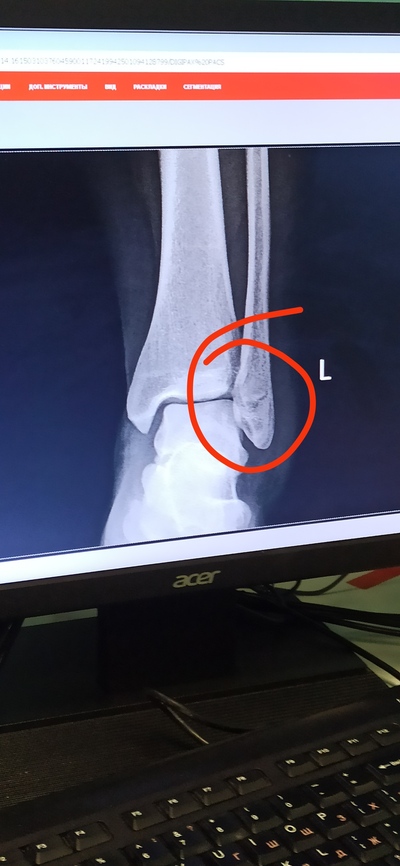

Поскользнулась (очнулась, гипс), закрытый перелом наружной лодыжки.

Пруфы, если надо. Ну мало ли, вдруг кто-нибудь дельного посоветует. И гипс буду менять.